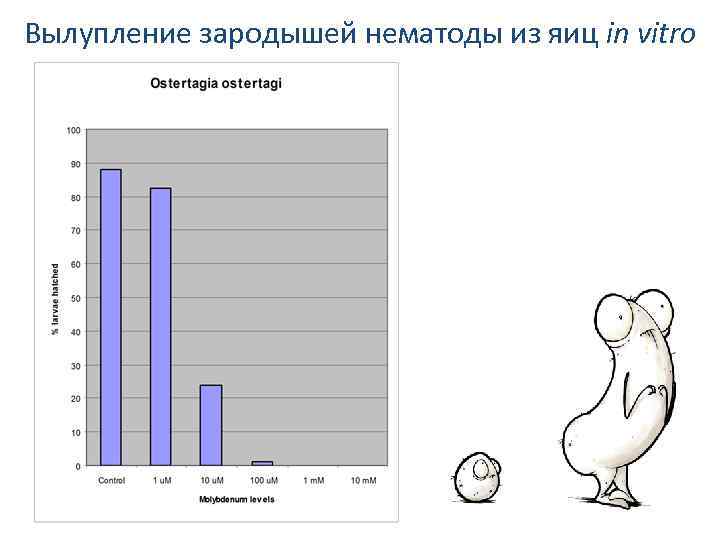

Вылупление зародышей нематоды из яиц in vitro

Тест развития личинок